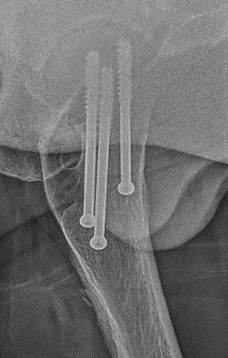

Cannulated screws

Technique

Lateral on traction table

- adequate reduction / no varus

- small incision or percutaneous

- 3 screws

- ensure inferior screw entry point is above lesser trochanter to prevent fracture

- ensure threads cross fracture site entirely to obtain compression

- need correct screw length so screw head can compress against cortex